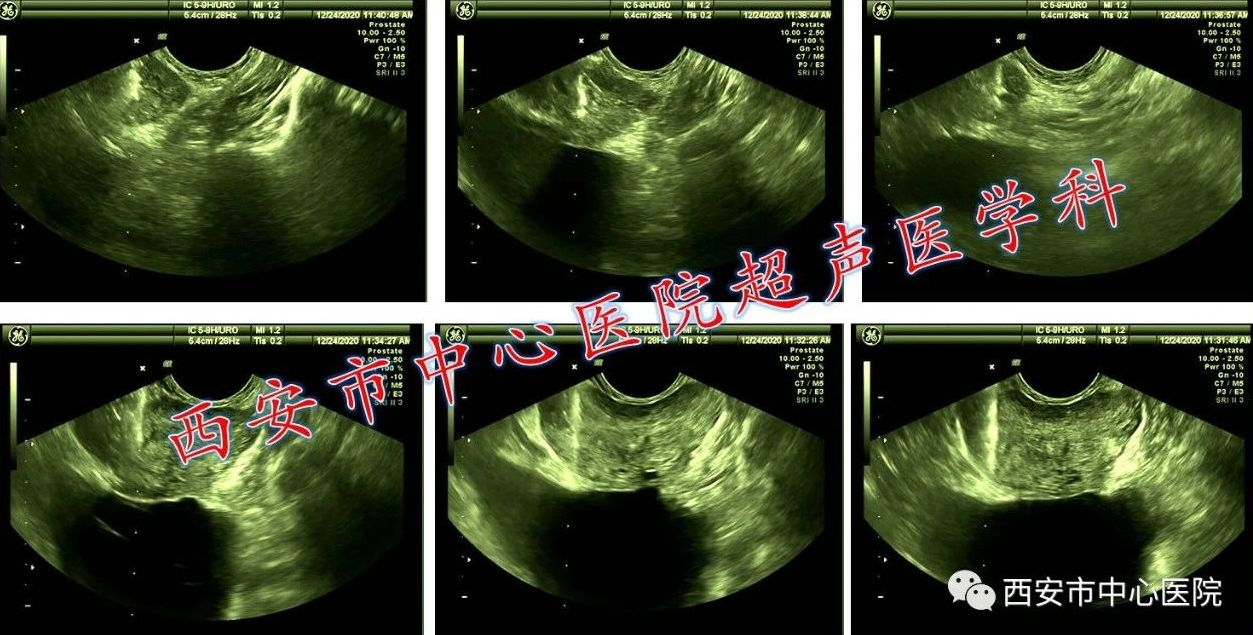

7. 腔内彩色多普勒超声引导下前列腺系统活检

前列腺癌经过手术、放疗等综合手段可以达到彻底治愈,早期诊断至关重要。传统诊断方法主要依靠直肠指诊(DRE)但漏诊率高。在高分辨率经直肠超声引导下进行系统穿刺是公认最佳的前列腺癌微创诊断方法。超声医学科已积累了百余例的超声引导下经直肠前列腺活检的穿刺经验,技术过硬,常规6针左右进行重点部位穿刺,穿刺阳性率高(92.33%),近年积极开展了12针+的系统前列腺穿刺方法,旨在实现“布满型”前列腺分区穿刺以提高早期前列腺癌及癌前病变的检出率。